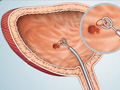

Transurethral resection of the prostate

Dr. Shk. Rezar Rusi

Transurethral Resection of the Prostate (TURP) is one of the surgical methods used for the treatment of benign prostatic enlargement (abbreviated from English as BPE or BPH) accompanied by urinary symptoms ranging from moderate to severe. TURP is performed using a combined visual-surgical instrument that is inserte...  read full article